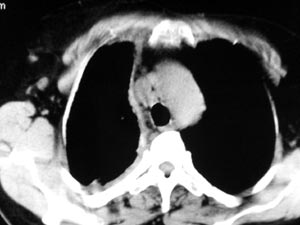

2 纵隔侧胸膜明显增厚

3 肋胸膜结节影

结合纵隔略宽、单侧胸水首先考虑肺癌。

考虑纵隔旁肺癌伴胸水可能。

右侧胸膜结节状增厚伴胸腔积液及纵隔、腋窝淋巴结肿大,考虑胸膜间皮瘤可能性大;建议胸膜活检。

右侧中央型肺癌合并阻塞性肺炎及右侧胸膜转移。